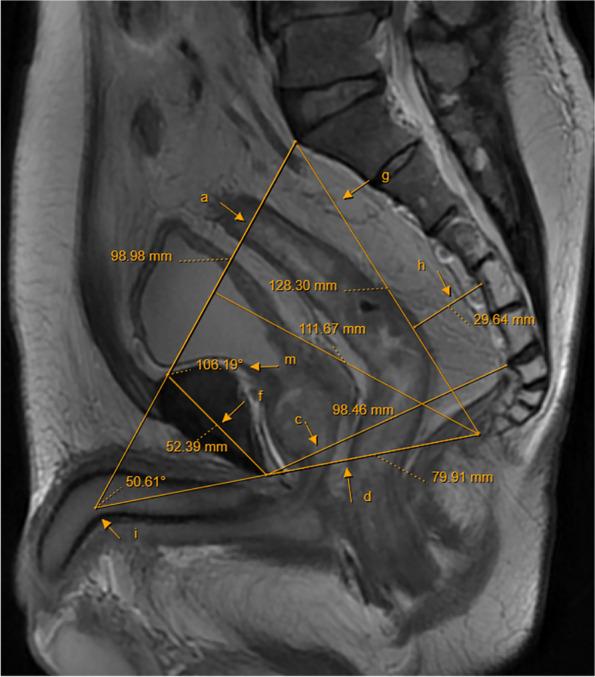

Advances in pelvic imaging parameters predicting surgical difficulty in rectal cancer.

Due to the fixed bony structure of the pelvis, the pelvic operation space is limited, complicating the surgical operation of rectal cancer, especially middle and low rectal cancer. The closer the tumor is to the anal verge, the smaller the operative field and operating space, the longer the operative time, and the greater the incidence of intraoperative side injuries and postoperative complications. To date, there is still no clear definition of a difficult pelvis that affects the surgical operation of rectal cancer. Few related research reports exist in the literature, and views on this aspect are not the same between countries. Therefore, it is particularly important to predict the difficulty of rectal cancer surgery in a certain way before surgery and to select the surgical method most suitable for each case during the treatment of rectal cancer.